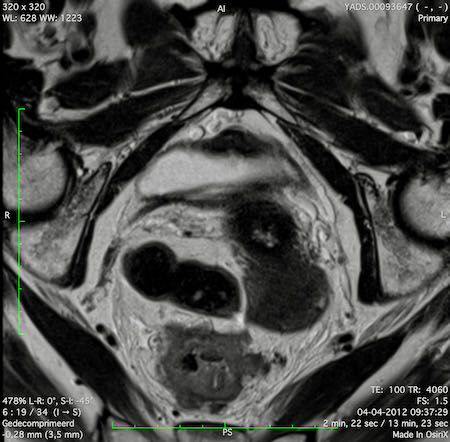

Hình ảnh

Các hình ảnh được cung cấp cho thấy ung thư biểu mô tế bào nhẫn với tình trạng dày lan tỏa thành trực tràng, hình ảnh bia bắn điển hình, và sự xâm lấn mỡ mạc treo trực tràng.